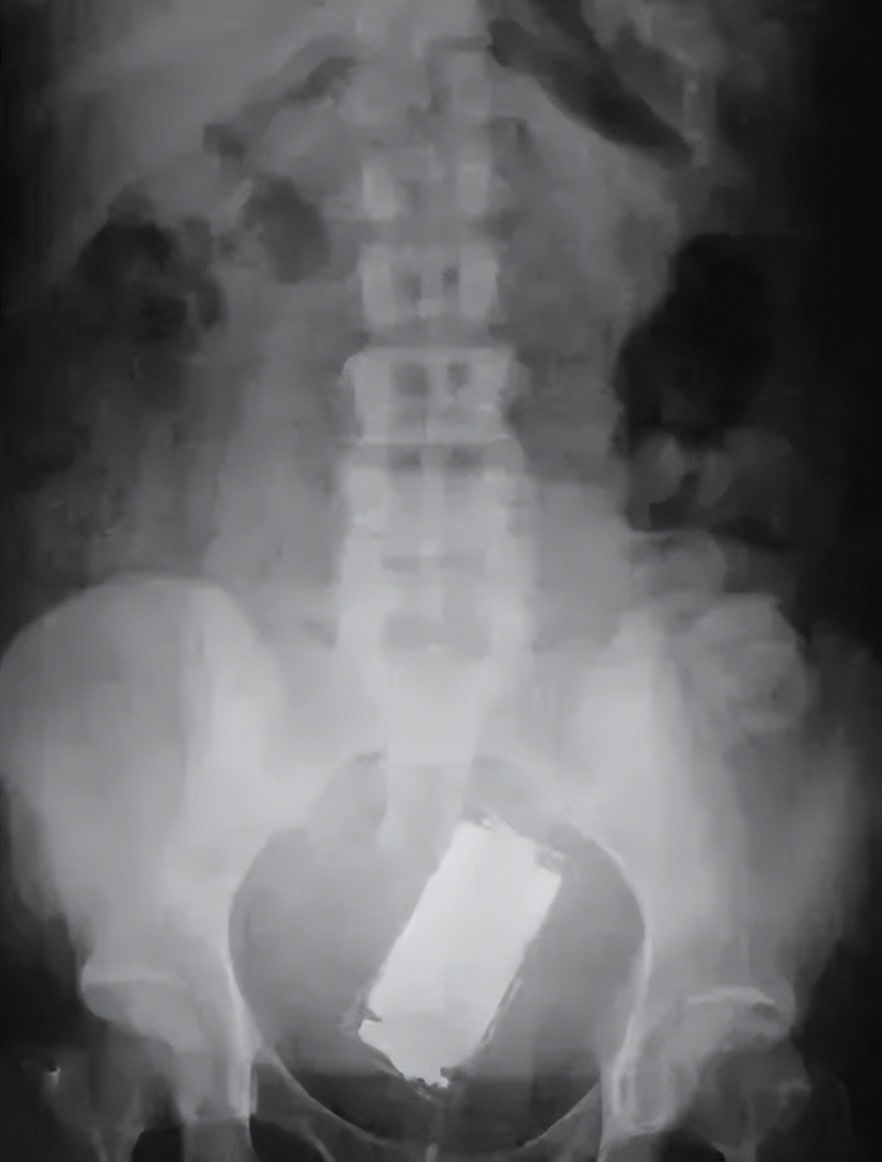

(不知道手机还有没有信号)